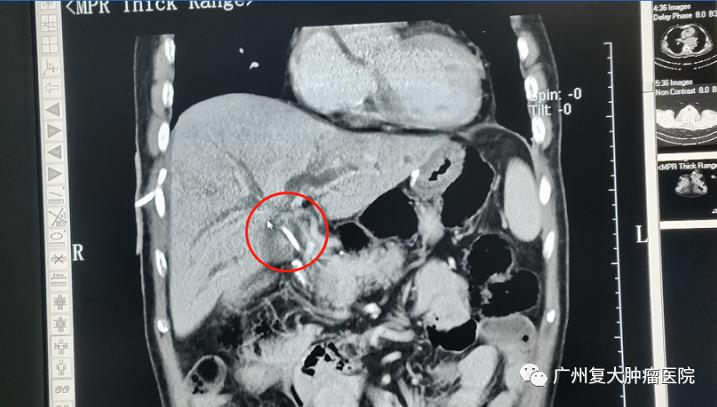

“只有解决了胆道梗阻,才能解决肿瘤。”介入科杨清峰主任表示,邹叔叔肿瘤虽不大,但长得位置却非常棘手,把肝胆管堵住了,这也导致他的黄疸一直降不下去。他的高位胆道梗阻是由肝门部淋巴结转移导致的,属于复杂性胆道梗阻,这种情况容易造成肝功能损伤。

▲肿瘤生长位置